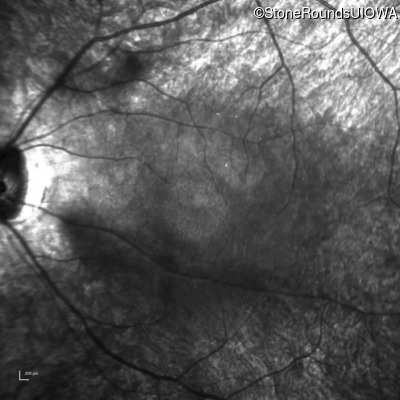

Infrared Fundus Photograph - Left - 20/100 -1

Exemplar